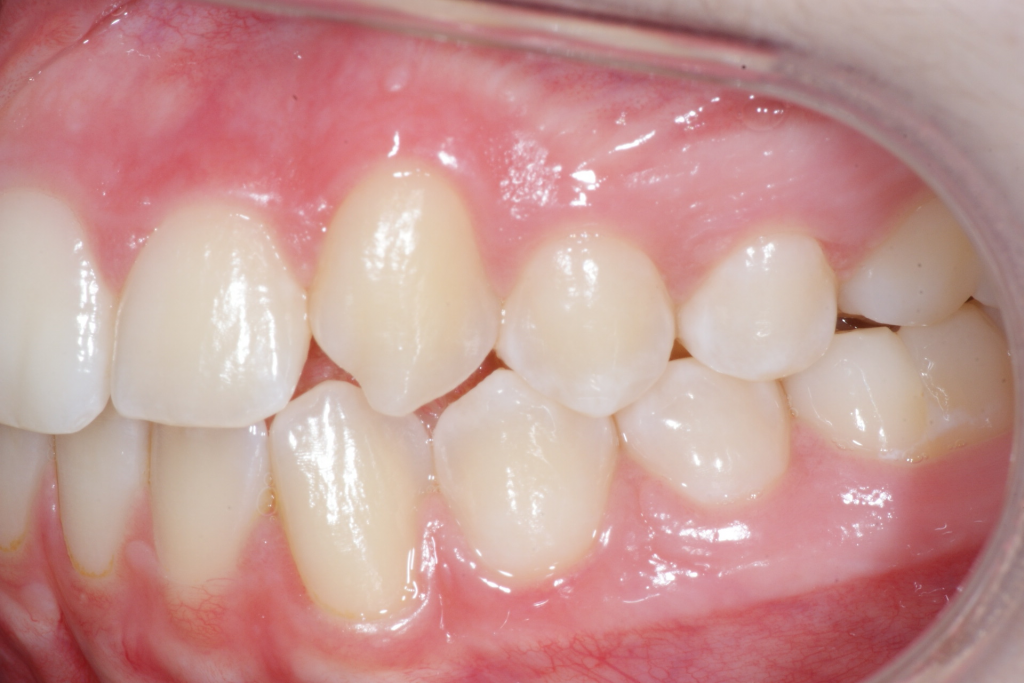

Correction d’une malocclusion de type Classe II subdivision avec canine ectopique (#14).  Des appareils fixes (boîtiers) et l’extraction d’une prémolaire (#15) furent nécessaires pour améliorer ce sourire.  Traitement chez une adolescente, réalisé en 21 mois.